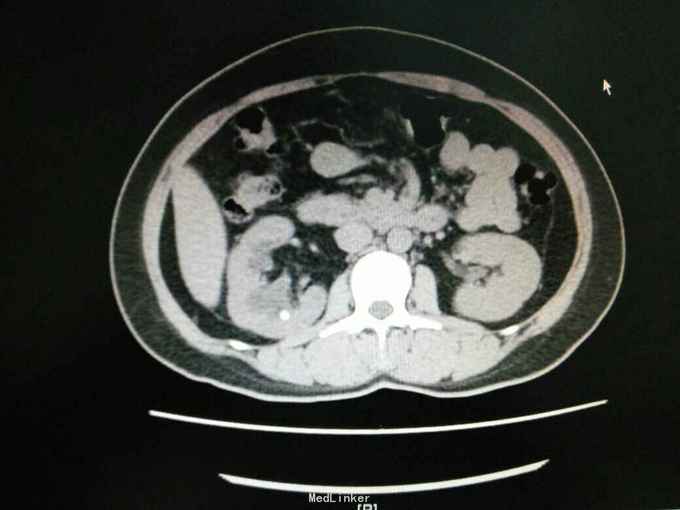

主诉:发现高血压升高10个月 病史:患者于10个月前无明显诱因出现头晕、头痛等高血压症状,血压最高达180/100mmHg,无尿频、尿急、尿痛,无排尿困难,无血尿、脓尿,在当地医院行CT提示肾上腺肿瘤,当时予以口服降压药治疗,并建议定期复查。现为进一步治疗收入我科。

查体:双肾区无红肿、隆起,无叩痛,双侧肋脊点、肋腰点无压痛。腹平软,双侧输尿管走行区无压痛,膀胱区无膨隆,压痛阴性,双侧腹股沟区未触及肿物。 辅查:外院CT提示肾上腺肿瘤

诊断:肾上腺肿物 治疗:完善常规检查及泌尿系B超、IVP、CT等检查; 完善WMA、17-羟、17-酮、醛固酮等肾上腺内分泌检查,暂给予降压治疗; 待检查汇报,可考虑行手术切除肿物。